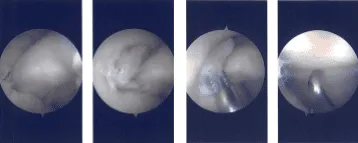

Intraoperative Arthroscopy Images

Then, the arthroscope was moved to the lateral compartment where a tear was seen. A medial entry portal was made with direct access to the left meniscus. The instruments were entered and the lateral margin of the medial meniscus, the fraying on the lateral margin of the medial meniscus was cleaned using a shaver.

The arthroscope was entered into the intercondylar area where there was partial tearing of the ACL fibers. The arthroscope was entered into the lateral femoral compartment where the tear was again seen. The third tear was thoroughly debrided using a shaver and straight bitter.

After the thorough debridement of the tear, the scope was moved into a patellofemoral joint where grade 3 to grade 4 osteoarthritic changes were seen. Chondroplasty of the posterior patellar surface was performed using a shaver.

There was grade 1 osteoarthritic change in the trochlea. was grade 1 to 2 osteoarthritic changes in the medial femoral compartment, medial femoral condyle posteriorly, which was shaved.

Now, the arthroscope was entered into the medial working portal and instruments were entered from the lateral portal. Final debridement of the lateral meniscus was performed. The knee was thoroughly irrigated and lavaged.